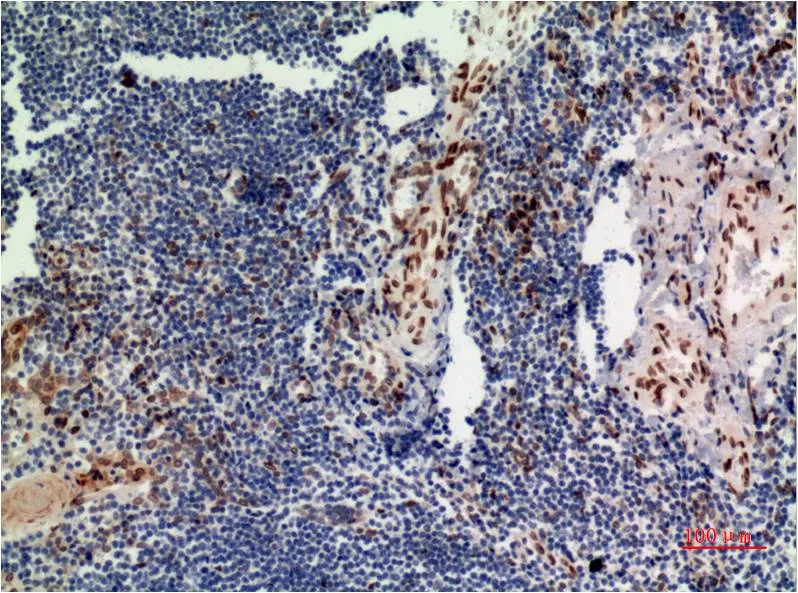

ERK1 (1D10) Mouse Monoclonal Antibody

Cat: AMM00760